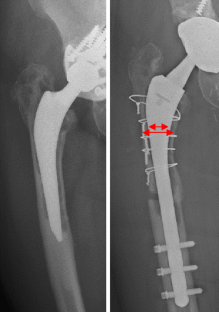

Fig. 1

Fig. 2

Fig. 3

Fig. 4